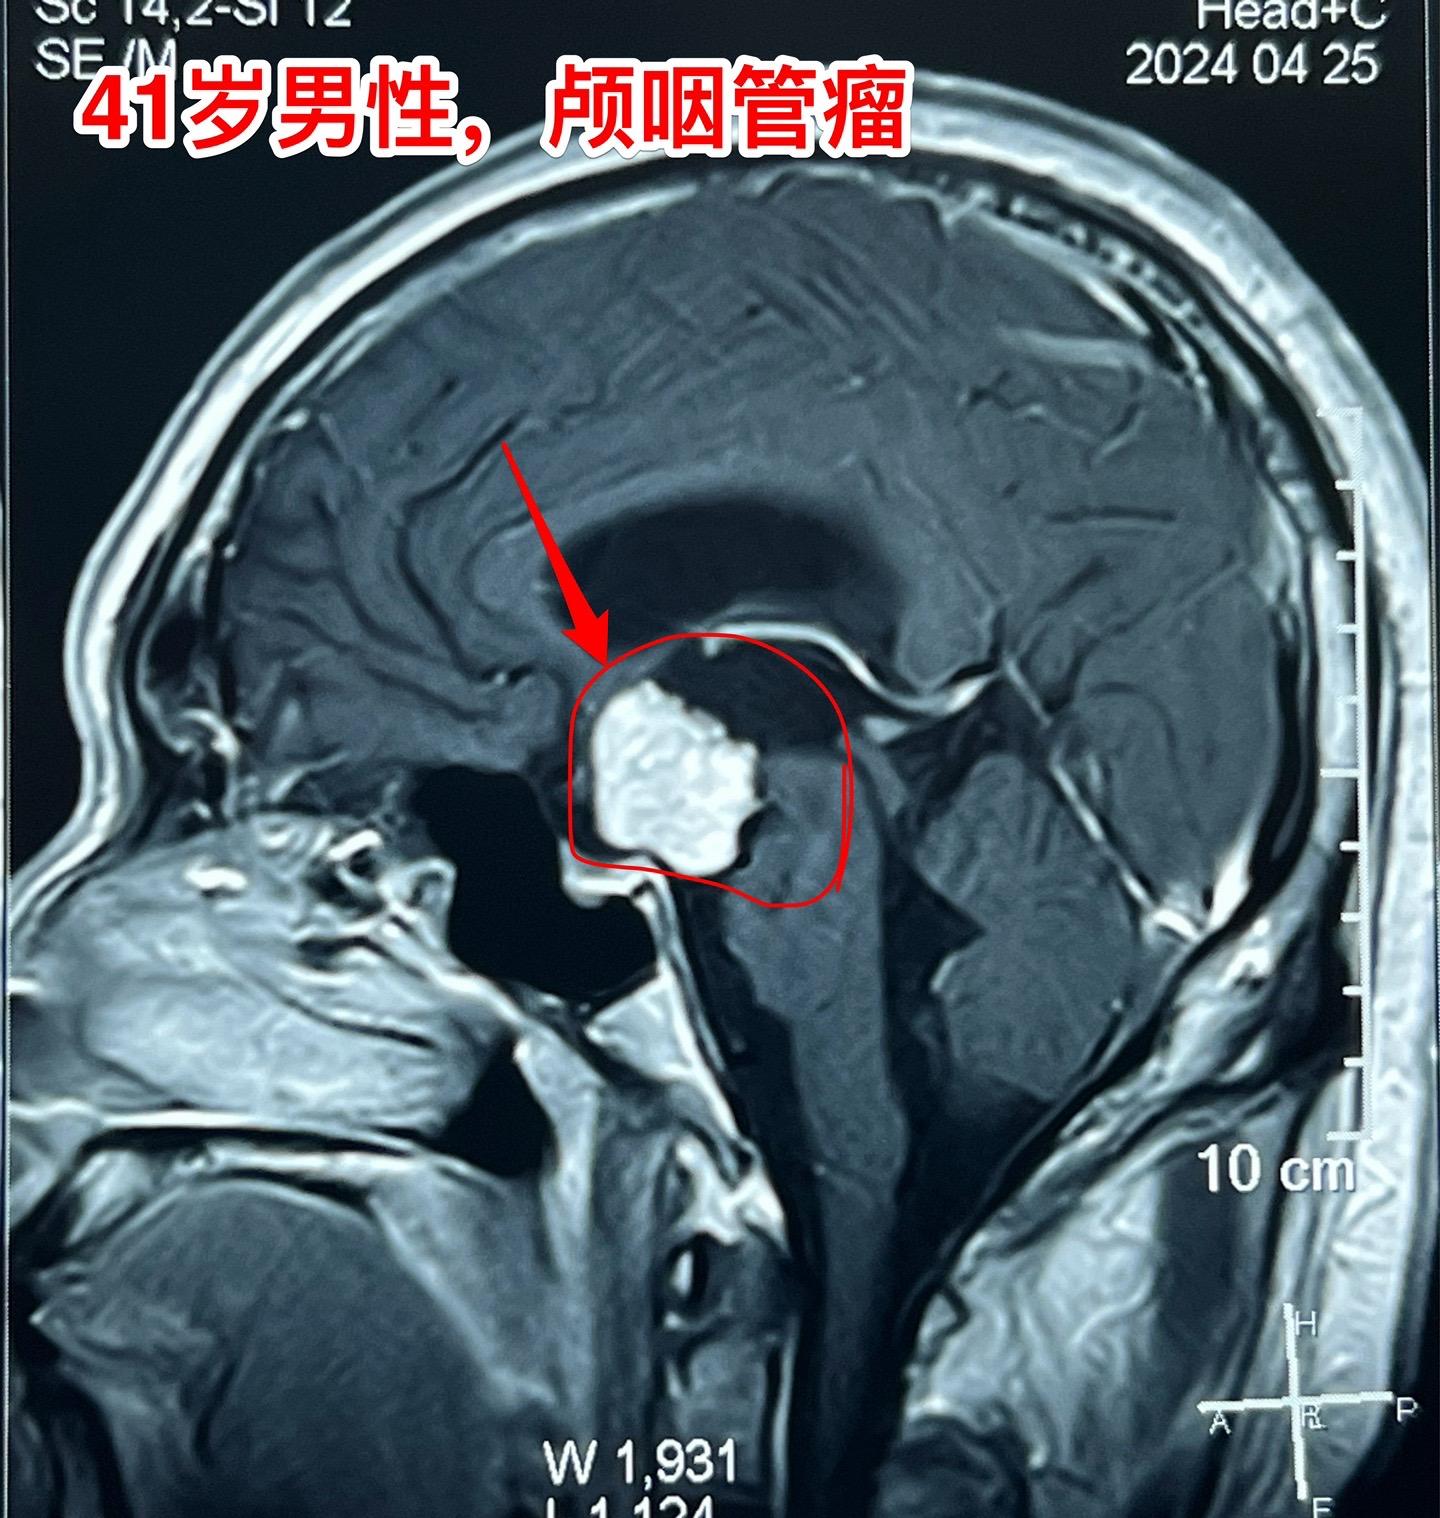

5月31日的颅咽管瘤手术。41岁山西男性,因思维糊涂、记忆力差发现鞍区肿瘤,为乳头型颅咽管瘤。

常规的经额底纵裂入路,将肿瘤完全切除。手术后病人的精神状态很好。

五月份的一共完成21台手术,其中20台为颅咽管瘤(今年一共80个颅咽管瘤手术),另一台为鞍区皮样囊肿!